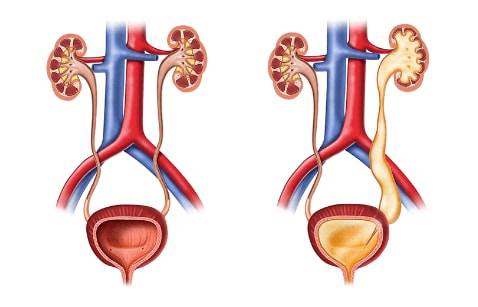

Η απόφραξη των ουροφόρων οδών είναι από τις συχνότερες παθήσεις του ουροποιητικού συστήματος.

Η στάση των ούρων που δημιουργείται, μπορεί να επιφέρει σημαντικές μεταβολές στη λειτουργία των νεφρών.

Η αποφρακτική ουροπάθεια αποτελεί μια συνήθη αιτία νεφρικής ανεπάρκειας, αλλά σημαντικό είναι, πως η κατάσταση αυτή είναι δυνητικά αναστρέψιμη με την κατάλληλη θεραπεία.

Ανεξαρτήτως του αιτίου, η στάση των ούρων προκαλεί διάταση της ουροφόρου οδού, κεντρικότερα της απόφραξης, με ουρολογικές, νεφρικές και συστηματικές επιπτώσεις.

Η κρισιμότητά της απόφραξης εξαρτάται από διάφορους παράγοντες, κυρίως από το επίπεδο που παρατηρείται το κώλυμα, αν αφορά στον έναν ή και στους δύο νεφρούς, καθώς και από τη διάρκειά της.

Η κλινική εμφάνιση και οι επιπτώσεις της αποφρακτικής ουροπάθειας ποικίλλουν ανάλογα με το επίπεδο της απόφραξης, την ταχύτητα της εγκατάστασής της και τη βαρύτητά της.